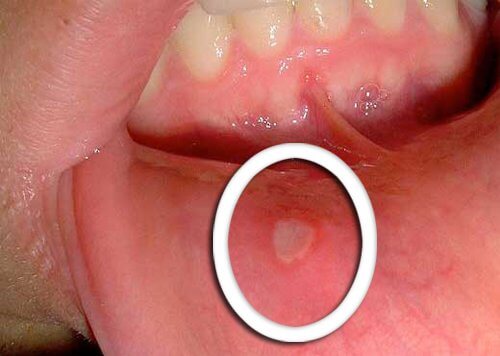

口内炎を治す